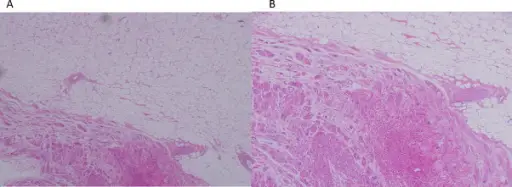

Rhabdomyoma

Rhabdomyomas are benign tumors composed of skeletal muscle.

Rhabdomyomas can develop in heart muscle, termed cardiac rhabdomyomas, which are associated with tuberous sclerosis.

Although rhabdomyomas are uncommon in general, they are the most frequent kind of cardiac tumor among infants and young children.